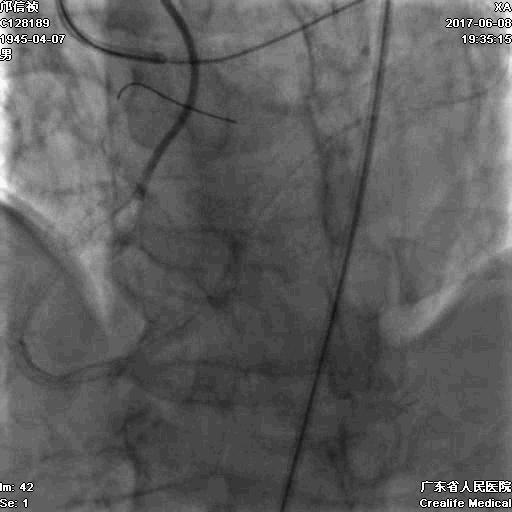

1.正向2.5*15mm球囊扩张,Reverse CART

2.Guidezilla延长导管辅助下,逆向导丝进入正向GC

1.更换RG3导丝

2.GC送入普通导丝,保护LM

支架术后造影结果